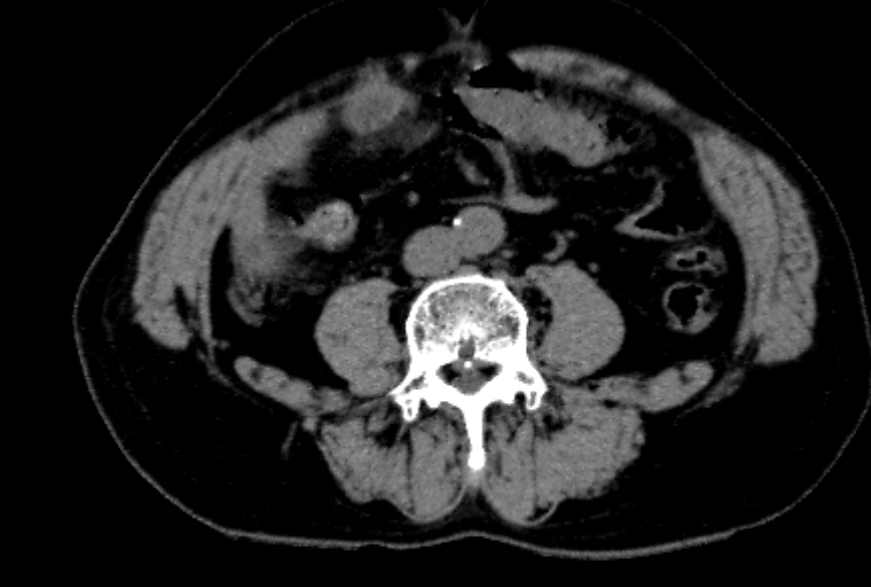

血常规白细胞:11.68*10^9/L,中性粒细胞比率89.5%,C反应蛋白26.46mg/L,血清淀粉样蛋白219.04mg/L。CT示:1.考虑阑尾炎性病变,请结合外科会诊及实验室检查2.升结肠周围脂肪间隙模糊,考虑炎性病变。

4.辅助检查:血常规白细胞:11.68*10^9/L,中性粒细胞比率89.5%,C反应蛋白26.46mg/L,血清淀粉样蛋白219.04mg/L。CT示:1.考虑阑尾炎性病变,请结合外科会诊及实验室检查2.升结肠周围脂肪间隙模糊,考虑炎性病变。